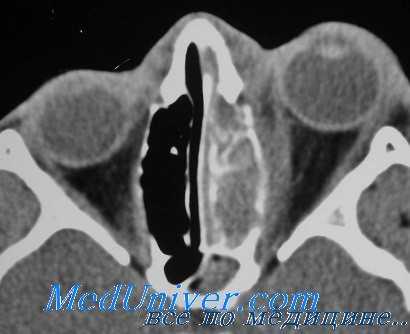

Хирургическое лечение остеомиелита плановое, абсцесса — срочное и начинается по возможности с четкой его локализации. Предположить местонахождение абсцесса можно либо по клиническим симптомам (абсцесс локализуется в зоне, противоположной смещению глаза; его репозиция за счет флюктуации гноя несколько свободнее, чем при целлюлите), либо по данным КТ или МРТ (топография абсцесса, его субпериостальное или орбитальное расположение). От этого зависят место кожного разреза и методика операции. Обязательные условия: все операции выполняют в условиях общей анестезии с использованием микрохирургической техники, разрез тканей проводят послойно.

Пресептальный целлюлит характеризуется воспалительным отеком тканей орбиты и век, незначительным экзофтальмом, однако подвижность глаза на этой стадии сохранена, а зрение не нарушено. Дальнейшее прогрессирование инфекционного процесса и его распространение в задние отделы глазницы вызывает развитие орбитального целлюлита. Эта форма клинически проявляется отеком век, экзофтальмом, хемозом, ограничением подвижности глазного яблока и снижением остроты зрения. Если гной скапливается между периорбитой и костной стенкой глазницы, приводя к разрушению последней, формируется субпериостальный абсцесс орбиты. На данной стадии отмечается отек и гиперемия верхнего века, нарушение подвижности и смещение глазного яблока в сторону, противоположную расположению абсцесса, экзофтальм, нарушение остроты зрения.

Субпериостальный абсцесс орбиты

Субпериостальный абсцесс орбиты – гнойное поражение стенки орбиты при воспалении околоносовых пазух. Заболевание характеризуется острым началом, повышением температуры до 39° С, отёком кожи вокруг орбиты, развитием хемоза конъюнктивы, появлением двоения, нарушением движений глазного яблока, резким снижением остроты зрения. Для диагностики применяют визометрию, биомикроскопию, тонометрию, периметрию, рентгенографию орбит и придаточных пазух носа, ультразвуковое исследование глаза и орбиты, КТ или МРТ орбит, придаточных пазух носа и головного мозга. Лечение консервативное (антибиотикотерапия, дезинтоксикационная терапия) и хирургическое (вскрытие, дренирование абсцесса).

Для диагностики применяют стандартные методы: визометрию, биомикроскопию, тонометрию, периметрию. Для точного определения локализации субпериостального абсцесса орбиты дополнительно используют лучевые методики. Рентгенография орбит и придаточных пазух носа в прямой и боковой проекциях позволяет диагностировать куполообразную (экссудативную) отслойку надкостницы орбиты и увеличение денситометрической плотности клетчатки глазницы вокруг очага воспаления.

Ультразвуковое исследование глаза и орбиты выявляет изменение размера ретробульбарного пространства, хода экстраокулярных мышц. КТ или МРТ орбит, придаточных пазух носа и головного мозга помогает определить отслойку периоста в зоне поражения. Кроме того, при субпериостальном абсцессе орбиты требуется консультация отоларинголога, челюстно-лицевого хирурга и нейрохирурга. Проводится бактериальный посев гнойного отделяемого с определением чувствительности к антибактериальным препаратам.